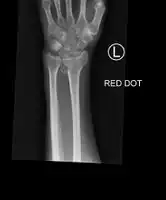

Bilateral Colles fractures/frontal

Colles fracture